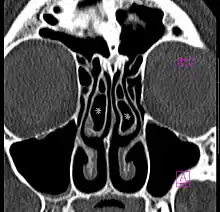

A concha bullosa is a pneumatized (air-filled) cavity within a nasal concha, also known as a turbinate.[1] Bullosa refers to the air-filled cavity within the turbinate.[1] It is a normal anatomic variant seen in up to half the population. Occasionally, a large concha bullosa may cause it to bulge sufficiently to obstruct the opening of an adjacent sinus, possibly leading to recurrent sinusitis[1] and various head pains related to areas innervated by the trigeminal nerve.[2] In such a case the turbinate can be reduced in size by endoscopic nasal surgery (turbinectomy). The presence of a concha bullosa is often associated with deviation of the nasal septum toward the opposite side of the nasal cavity.[3]

Some experts call pain associated with enlarged concha bullosa "rhinogenic contact point headache."[4] In a review article of fifteen other journal articles of surgeries, significant improvements occurred after surgical treatment with a reduction from 88 (73%) to 6 (5%) patients for GRADE 3–4 MIDAS scores,[5] and a corresponding increase in milder symptoms from GRADE 1–2 in 32 (27%) patients at 91 (76%) (p < 0.001).